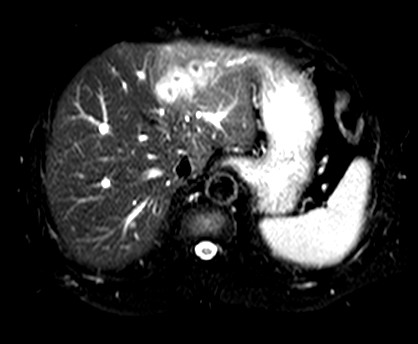

标题: CT19720:肝右叶血管瘤。肝左叶内侧段病灶考虑什么? [打印本页]

标题: CT19720:肝右叶血管瘤。肝左叶内侧段病灶考虑什么?

男,48岁,肝区不适月余,伴隐痛。

支持右叶血管瘤,左叶病灶考虑肝腺瘤。

1)不排除肝左叶肝癌。2)肝右叶血管瘤。

肝左叶炎性病变,肝癌待排。2)肝右叶血管瘤。

1.肝右叶血管瘤;2.肝左叶炎性假瘤?肝癌?建议穿刺活检.

右叶病灶典型,左叶病变慢性炎块

1、肝右叶血管瘤(典型)。

2、肝左叶病灶,强化不明显,疑炎性假瘤,建议结合临床并密切随访。

1、肝左叶炎性病变,肝癌待排。

2、肝右叶血管瘤。

肝左叶脓肿,肝癌待排。2)肝右叶血管瘤